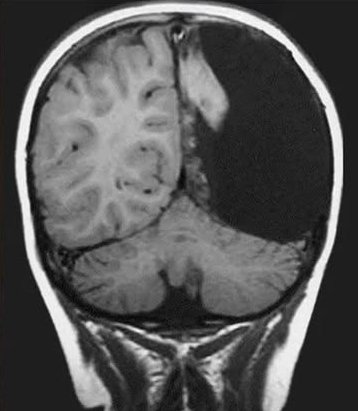

At the age of 8, Christina Santhouse underwent surgery to remove half of her brain. The procedure was performed by the renowned Dr. Ben Carson.

She had a neurological disorder in which her immune system attacked her brain cells, leading to relentless seizures.

Doctors warned her family that she might never speak, walk, or function independently again.

Against all odds, Christina not only recovered, but she also went on to earn her driver's license at 17 and completed both a bachelor's and a master's degree in speech pathology within five years.

Today, she works helping children overcome communication challenges, a career inspired by her own journey.